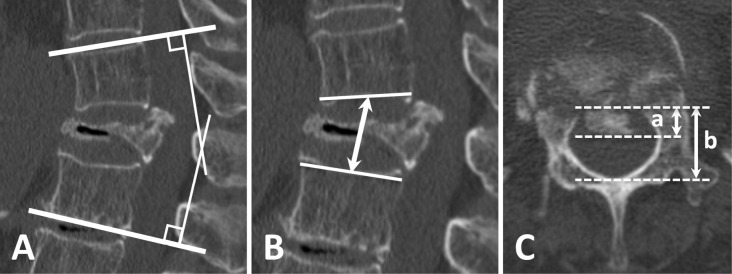

Methods: A total of 17 patients who underwent lateral and posterior combined indirect decompressive spinal reconstruction (LP-IDR) for single-level OVF with neurological symptoms were included in this study. The neurological symptoms (sensory disturbance and muscle weakness) and imaging findings (local angle and height of the fracture segment and bone fragment occupancy in the spinal canal) were investigated preoperatively, postoperatively, and at the 1-year follow-up.

Results: Muscle weakness was observed preoperatively in ten patients. Nine patients had complete recovery of muscle weakness (p<0.001), whereas one had residual muscle weakness at the 1-year follow-up. The presence of sensory disturbance was observed in 16 patients preoperatively, and it was significantly reduced to 8 patients at the 1-year follow-up (p=0.003). The bony fragment occupancy rate in the spinal canal was decreased from 44.0% to 40.2% postoperatively (p=0.04) and to 33.1% at 1 year (p=0.002). The local angle was corrected from 8.3° to -2.6° postoperatively (p=0.003) and to 1.2° at 1 year. The local height was corrected from 26.7 to 32.0 mm postoperatively (p<0.001) and to 29.8 mm at 1 year.